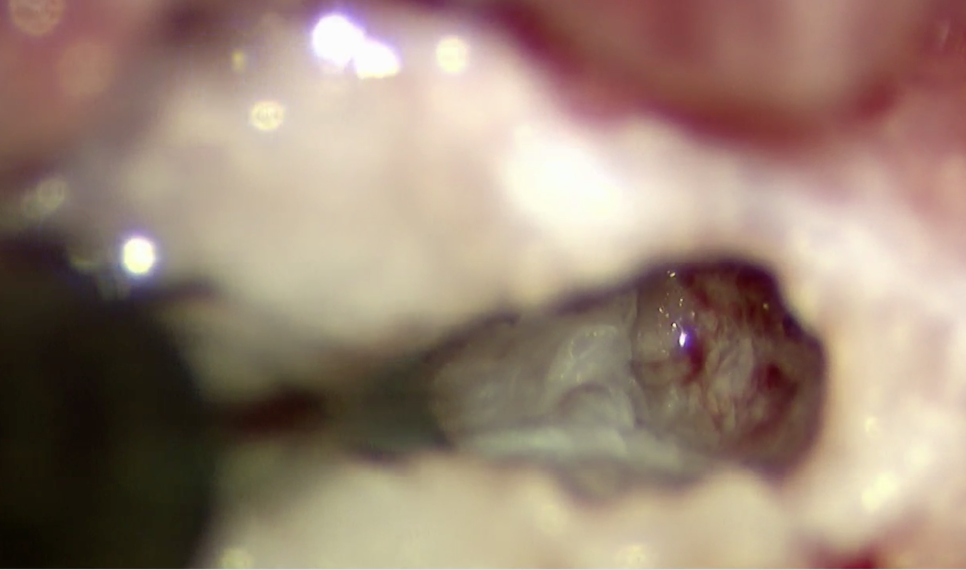

椎間板物質が摘出され、一番奥に神経が見えています。

椎間板物質をすべて摘出すると神経が見えてきます。押されている様子などがなければ終了として閉創して終了となります。